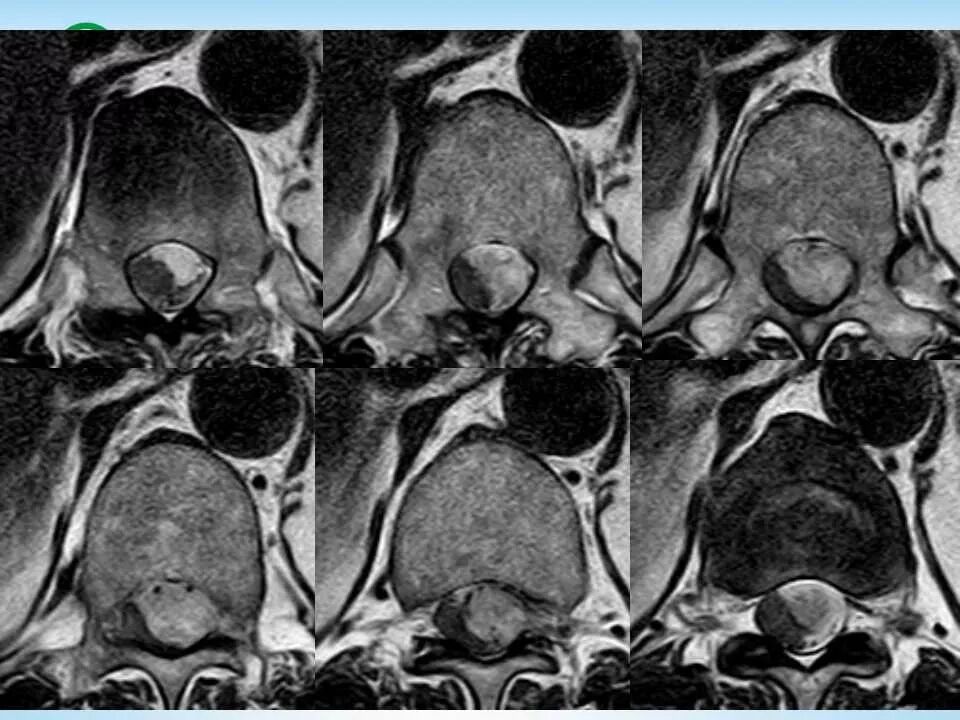

北方影像联盟 一周病例精选之“椎管占位”